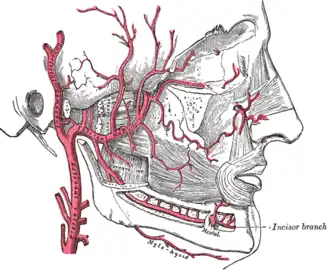

The pterygoidei; the zygomatic arch and a portion of the ramus of the mandible have been removed. (Internus is visible at center bottom.) | |

Plan of branches of internal maxillary artery.

Plan of branches of internal maxillary artery. -